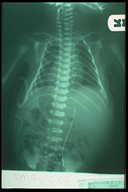

Lateral chest X-ray in Pectus excurvatum